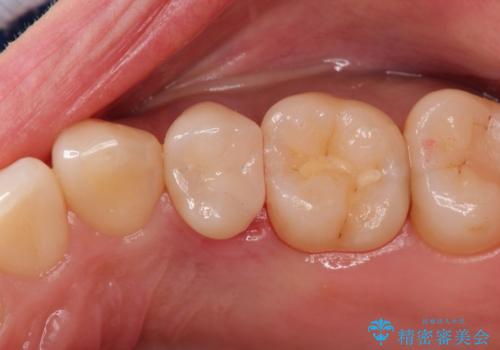

- 以前に前歯を折れた時、コンポジットレジンで修復したが、変色してきたことを主訴に来院されました。

今回は、セラミッククラウンによる修復を希望され、治療を行っています。

コンポジットレジンは、経年変化しやすい材料ですが、セラミックは変色しずらい材料となります。